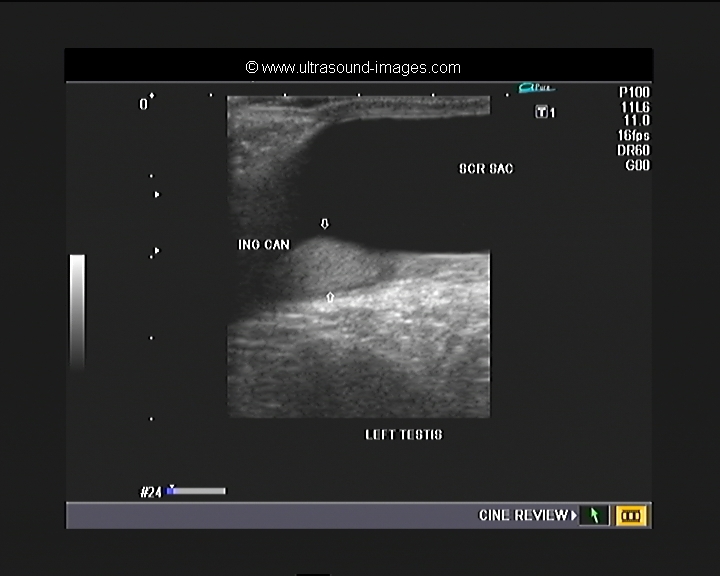

inguinal testis

this is an example of the left inguinal testis (see ultrasound images of left inguinal testis below). in this infant, aged two months, the baby has normal rights testis located within the scrotal sac. However, the left testis is located low down within the left inguinal Canal suggesting left cryptorchidism or left undescended testes. Also evident is communicating hydrocele of the left side. Normal vascularity is present in the left testes suggesting that this testis is viable.